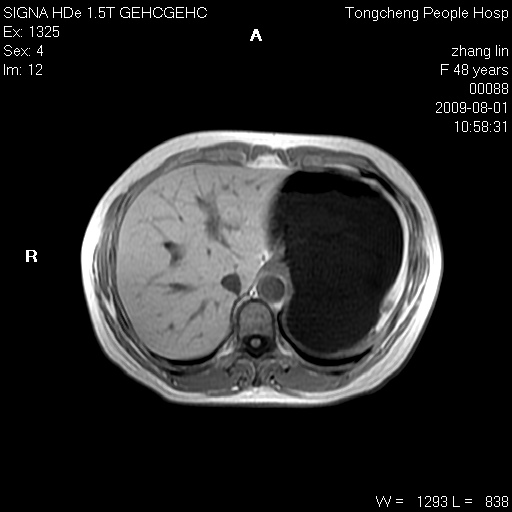

女,48岁。健康体检,彩超发现右肾占位性病变。平素健康。

临床诊断:右肾占位性病变,性质待定(囊肿?肿瘤?)。

上中腹部mr平扫+增强扫描,图像如下:

右肾上极见一类圆形病灶,t1wi呈等信号t2wi呈等高混杂信号,三期增强无强化,边界清---考虑囊肿出血。